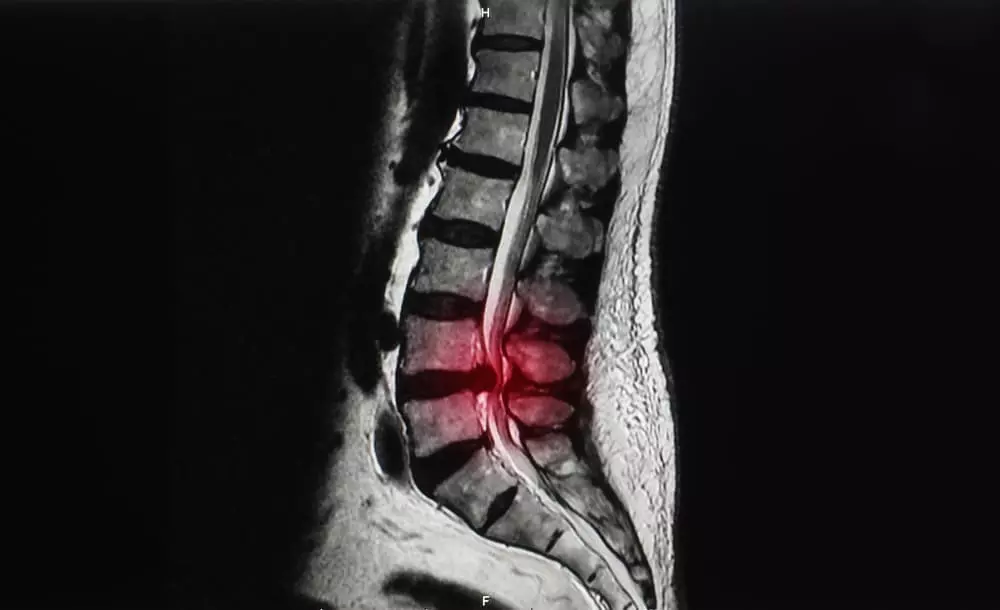

背骨は、32から34個の椎骨が連なってできています。

その中には空洞があり、脊髄や血管が通る脊柱管と呼ばれる通路があります。

この脊柱管が何らかの理由で狭くなり、神経を圧迫することで、痛みやしびれといった症状が現れるのが脊柱管狭窄症です。